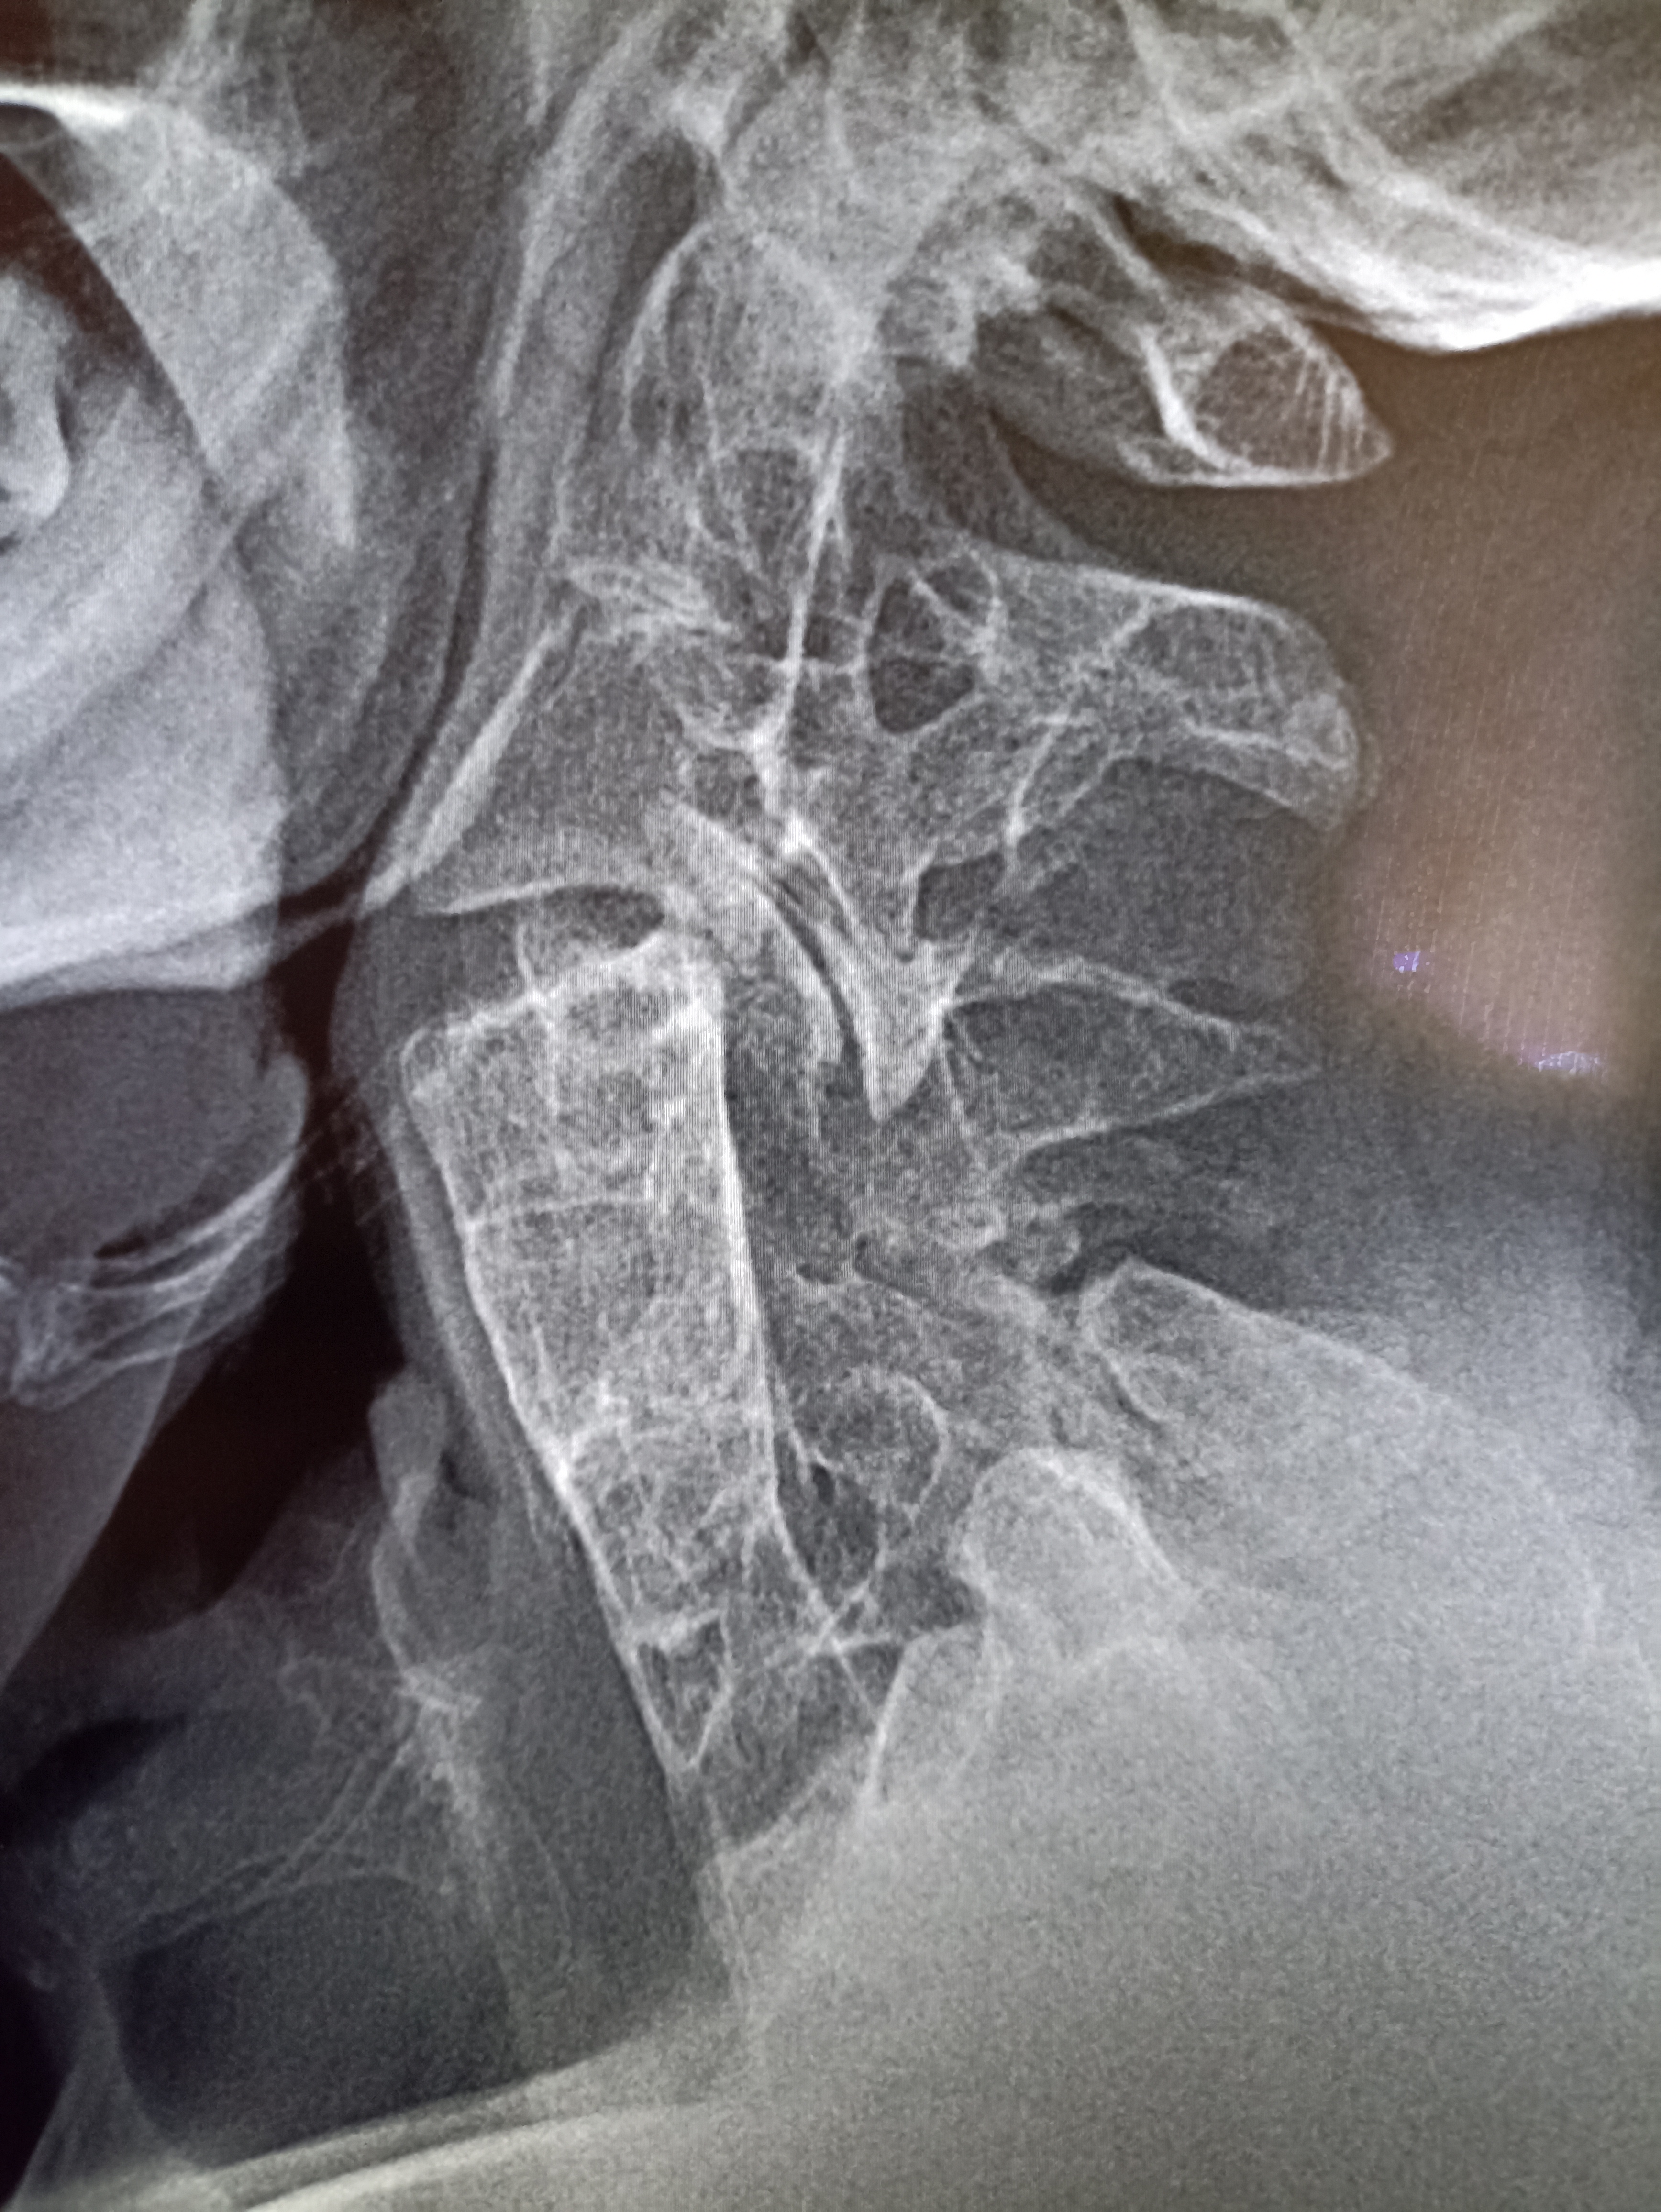

IMG20251009125406.jpg

Где пиздецома?

IMG20251008112937.jpg

>>325599324

тут очевидный гиперостеохондроз